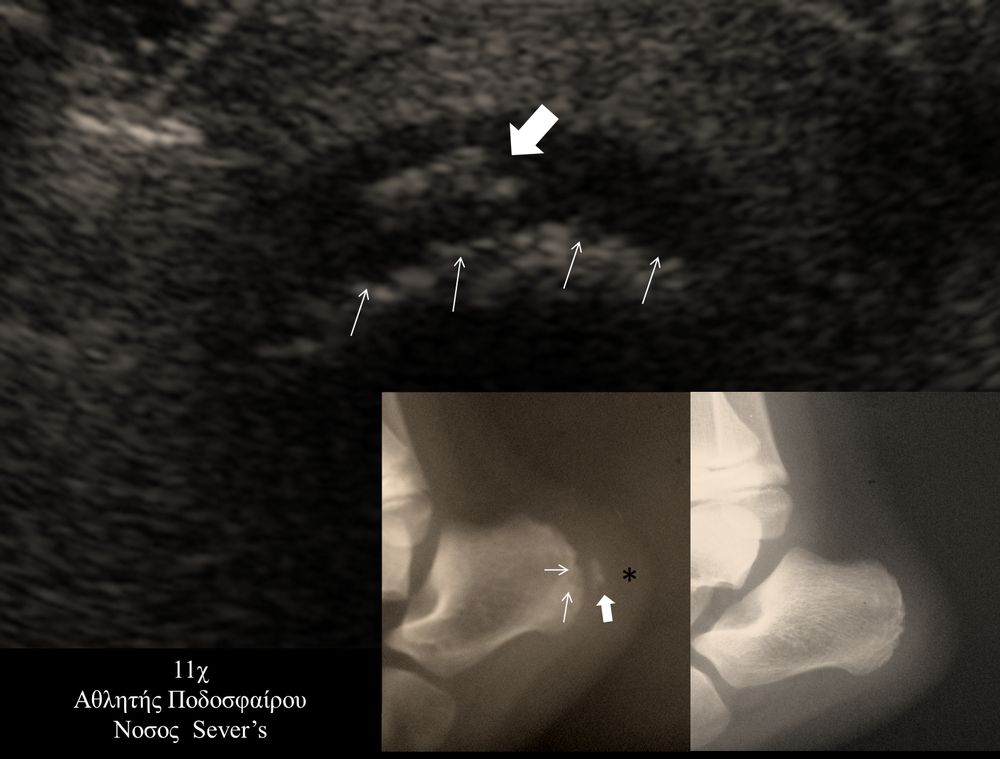

- Αθλητικές κακώσεις σε παιδιά (πχ αποφυσίτιδα)